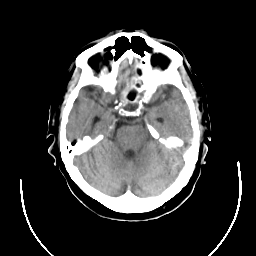

CT Study #3 -- Slice #9